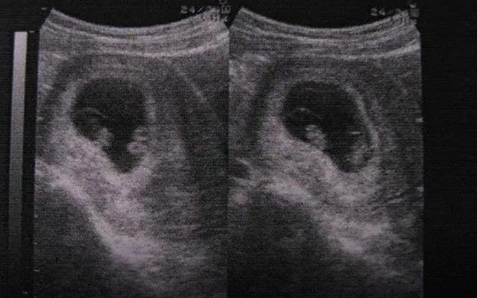

1、同卵双胞胎:这是指由一枚受精卵分裂成两个胚胎发育而成的双胞胎,一般是共用一个孕囊和胎盘。这种情况意味着同卵双胞胎的宝宝基因完全相同,性别也基本相同,而且他们在外貌、智力以及性格等方面都非常相似,甚至可能难以区分。

2、异卵双胞胎:这是指由两枚独立的受精卵分别发育而成的双胞胎,形成的受精卵是独立的,发育成胚胎也是独立的,拥有两个独立的孕囊以及胎盘等组织。这种情况意味着异卵双胞胎的基因不完全相同,同时,他们的外貌、性别和智力可能有很大的差异。

由此可见,使用b超进行检查的时候,如果存在双胞胎的情况,是同卵双胞胎还是异卵双胞胎,能够一眼就看出来区别。当然,需要注意的是,怀孕35天时期,还属于比较早的妊娠初期,只有部分孕妇能够发现,且只能确定是早孕,大部分的女性都无法分辨和确定是单胎还是双胞胎,一般需要等到6-7周左右,才能进行最终的判断。